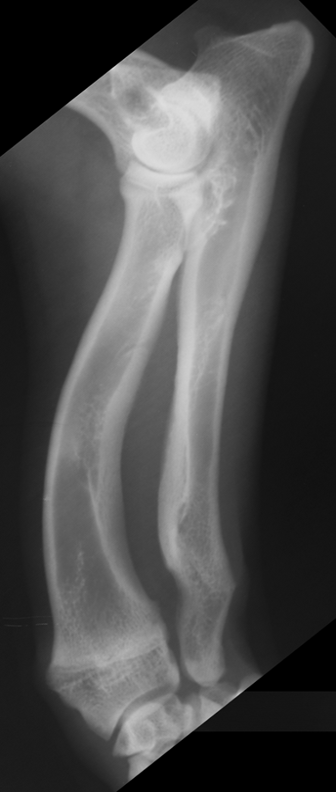

premature distal ulnar physis closure roentgen signs

gap - ulna and humerus, and gap at the bottom of ulna and carpus

cranial bowing of radius

premature distal radius physis closure roentgen signs

gap - radius and humerus, radius and carpus

no real ALD

which physis closed early

ulna

radius